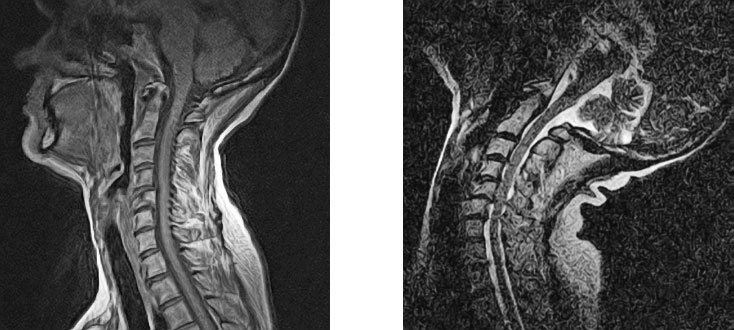

Специальные изменения в позах могут понадобиться людям с ампутированными конечностями, пациентам после инсульта и тем, у кого ограничены те или иные физические возможности. Например, при стенозе шейного отдела позвоночника не рекомендуется наклонять голову назад (изображение МРТ на рисунке 25 иллюстрирует возможный риск). Кроме того, обучая очень молодых людей, правильнее сосредоточиться на общей позе без дотошной корректировки деталей, поскольку она может быть воспринята как критика и лишит ученика всякого желания продолжать занятия. Для них гораздо полезнее выполнять упражнения с удовольствием, чем соблюдать все детали. В таких случаях компетентный учитель или терапевт станет ценным источником мудрости и безопасного обучения.

Иллюстрация к книге — Йога при остеопорозе [_28.jpg]

Рисунок 25. Запрокидывание головы значительно уменьшает диаметр и без того суженного позвоночного канала, приводя к спондилолистезу на уровне V шейного позвонка (удлиненный верхний позвонок – это II шейный). Сравните практически нормальный, слегка суженный канал в нейтральном положении (слева) и опасно сжатый спинномозговой канал при наклоне головы назад (справа). Опытные преподаватели с особой осторожностью следят за выполнением положений на сильную растяжку.